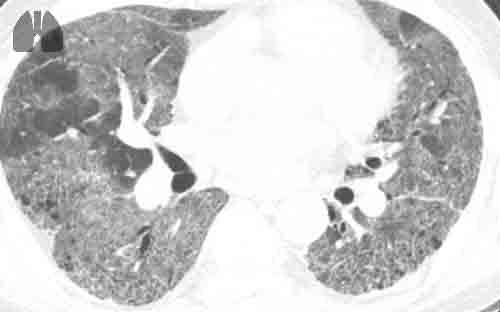

a) Initial CT scan: images show extensive ground-glass opacities in both lungs with subpleural predominance affecting 50–75% of lung parenchyma, as well as condensation in the right lower lobe. b) Control CT imaging at day-10 : axial CT images show extensive honeycombing cysts associated with septal thickening, with subpleural predominance (where ground-glass opacities had initially been observed, notably in the right lower and upper lobes), with associated traction bronchiectasis. Pneumomediastinum also developed. There was no sign of pulmonary embolism.

On day-10, because the patient still required high levels of oxygen via high-flow nasal cannula, a control CTPA was performed. It showed no evidence of pulmonary embolism, but rapid onset of extensive pulmonary honeycombing fibrosis in the territories where ground glass opacities had been present. Multidisciplinary meeting concluded that rapid onset pulmonary fibrosis complicated the course of severe Covid-19 pneumonia. Search for other causes of interstitial lung disease including autoimmune disease was negative. Treatment included daily high-dose intravenous corticosteroids boluses of 250 milligrams for three days, followed by 1 milligram per kilogram per day, associated with antifibrotic therapy with nintedanib. The patient's condition improved and he was transferred to pneumology wards on day 18 on oxygen therapy (6 L·min−1).